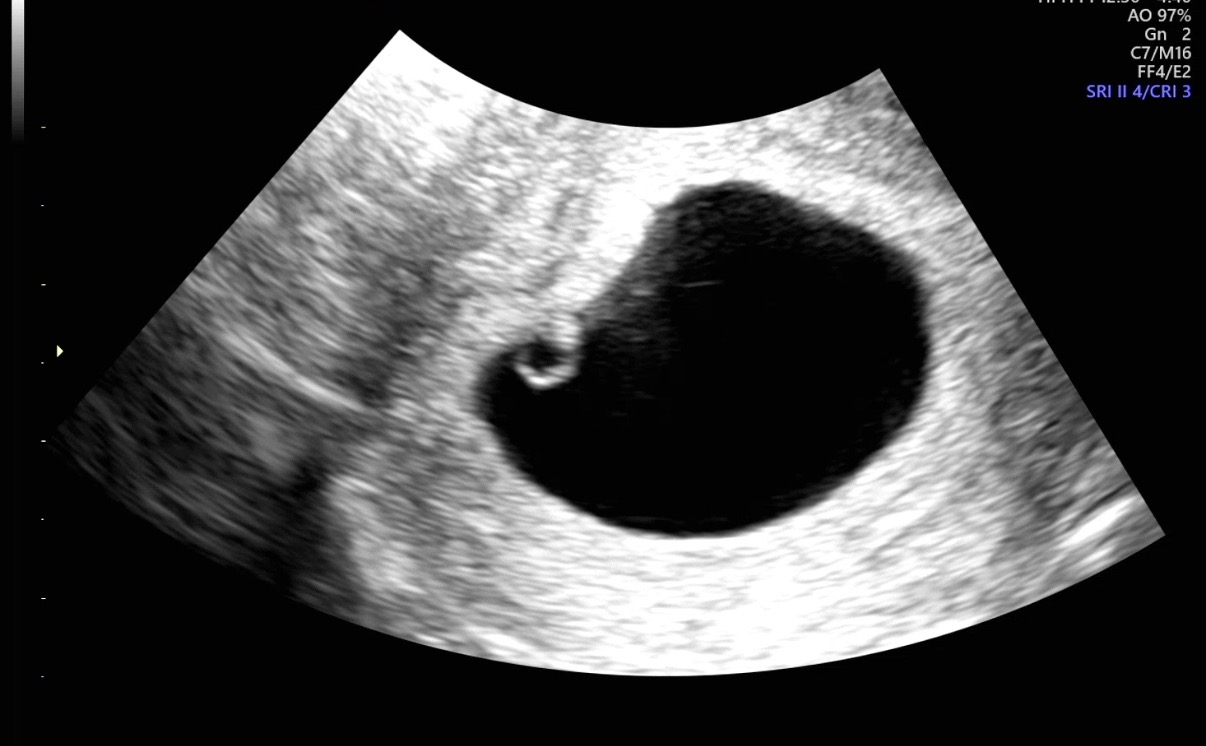

| 가슴 떨리는 임신 이야기를 공유해 주세요. | 자연임신을 6개월 시도하고, 배란유도제 복용과 난포 주사도 6개월 동안 진행했지만 매번 임신테스트기 한 줄을 보며 ‘내 인생에 아기는 없는 걸까’라는 생각까지 들었습니다. 하지만 서울아이비에프여성의원에서 포기하지 않고 치료를 이어간 끝에 저도 임신의 기쁨을 느낄 수 있었습니다. 시험관 시술 전에는 많이 두렵고 망설였지만, 막상 시작해보니 ‘왜 더 빨리 하지 않았을까’라는 생각이 들었습니다. 임신테스트기 두 줄, 아기집 확인, 심장 소리까지 아직도 실감이 나지 않을 만큼 새로운 감정을 경험하게 되었습니다. |

| 치료 도중 느꼈던 가장 기뻤던 순간과 절망적인 것들은 무엇인가요? 잊지 못할 경험이 있나요? | 가장 기뻤던 순간은 임신 확인 후 처음으로 심장 소리를 들었을 때입니다. 가장 힘들었던 순간은 호르몬 수치가 맞지 않아 시험관을 결심하고도 시술을 바로 시작하지 못했을 때였습니다. |